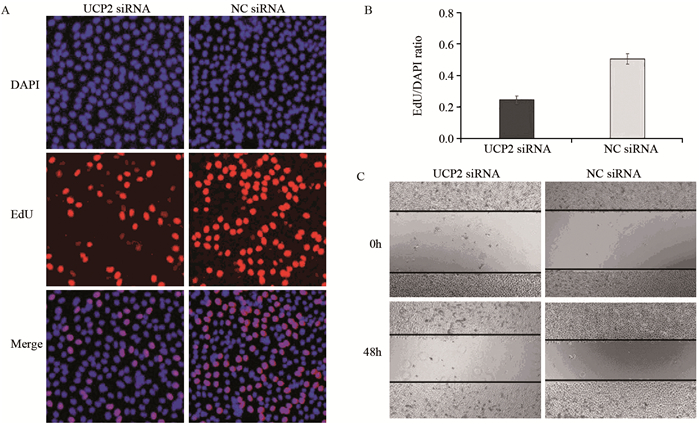

方法免疫组织化学法检测142例胃腺癌及25例癌旁正常胃黏膜组织中UCP2的表达情况,Pearson χ2检验分析其与临床病理特征的关系,Kaplan-Meier法及Cox风险回归模型分析UCP2的表达与胃腺癌患者预后生存的关系。将UCP2 siRNA转染SGC7901胃腺癌细胞系后,Western blot法检测UCP2蛋白的表达,EdU实验检测细胞增殖,划痕实验检测细胞迁移能力。

结果在胃腺癌组织中UCP2蛋白的阳性表达率明显高于癌旁正常胃黏膜组织(P=0.006),UCP2蛋白的表达与肿瘤浸润深度(P=0.024)、TNM分期(P=0.002)、淋巴结转移(P=0.001)显著相关;UCP2阳性患者5年生存率明显低于阴性患者(P=0.001)。在胃腺癌SGC7901细胞系中,UCP2高表达,沉默UCP2的表达能显著抑制肿瘤细胞的增殖,同时降低其迁移能力。

MethodsTotally 142 cases of gastric cancer and randomized 25 cases of normal gastric mucosa tissues in Tianjin Medical University Cancer Institute and Hospital were included. We used immunohistochemical staining to detect the expression of UCP2 and analyze its relationship with clinical pathological features. Kaplan-Meier method and Cox regression analysis were used to explore the correlation between the expression of UCP2 and the survival of gastric cancer patients. Western blot was used to detect UCP2 protein level after UCP2 siRNA transfection into SGC7901 gastric cancer cell lines. EdU assays and scratch assay were used to detect the proliferation and migration abilities.

ResultsThe expression of UCP2 in gastric adenocarcinoma tissues was significantly higher than that in adjacent normal tissues (65.5% vs. 28%, P=0.006). The expression of UCP2 in gastric adenocarcinoma tissues was significantly correlated with tumor infiltration (P=0.024), TNM stage (P=0.002) and lymph node metastasis (P=0.001). The 5-year overall survival of patients with positive UCP2 expression was significantly lower than those without UCP2 expression (P=0.001). Silencing UCP2 expression could significantly inhibit the proliferation and migration abilities of SGC7901 cell lines.

ConclusionPositive UCP2 expression is a prognostic factor of gastric adenocarcinoma patients. UCP2 could stimulate the proliferation and migration of gastric cancer cells.